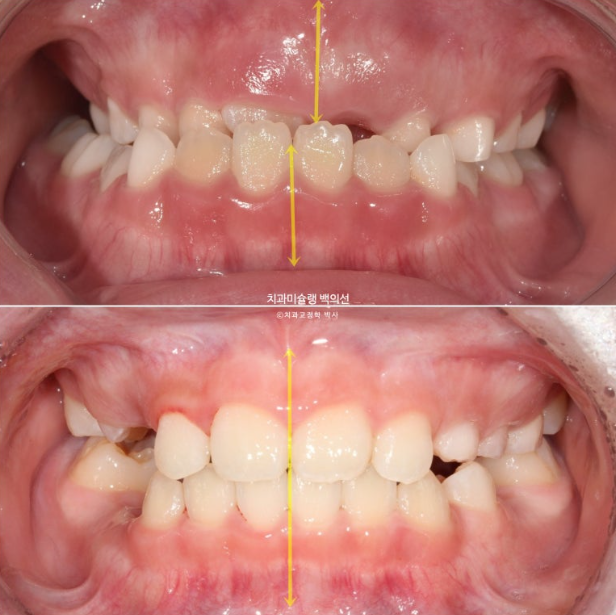

2022년 8월 내원한 어린이 입니다.

앞니 반대교합과 비대칭 치료를 위해 오셨습니다.

앞니 뿐 아니라 송곳니, 일부 어금니까지 거꾸로 물리는 상황입니다.

앞니 반대교합은 프리올소와 같은 장치로 간단하게 넘겨줄 수 있지만 더 큰 문제는 비대칭입니다.

아래앞니와 함께 아래턱이 우측으로 돌아가 있습니다.

골격분석 결과 페이스마스크와 같이 적극적인 주걱턱 치료는 불필요하고 가성주걱턱일 가능성이 높아 간단하게 반대교합 부터 넘기기로 합니다.